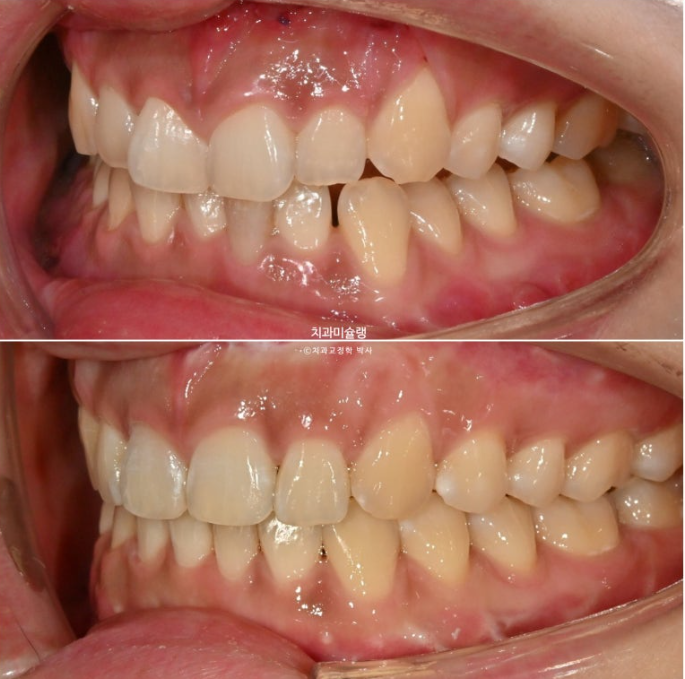

선수술 후 한달간의 회복기를 거쳐 25년 1월 본원에 내원했을 때의 교합 상태입니다.

25.01

앞니 두 개는 나비치아 돌출이며

어금니 교합이 떠있습니다.

앞니에 배열이 삐뚤합니다.

중심선은 정확히 맞으며

어금니 교합은 물샐틈 없는 1급 교합관계를 보입니다.

25.02~25.10